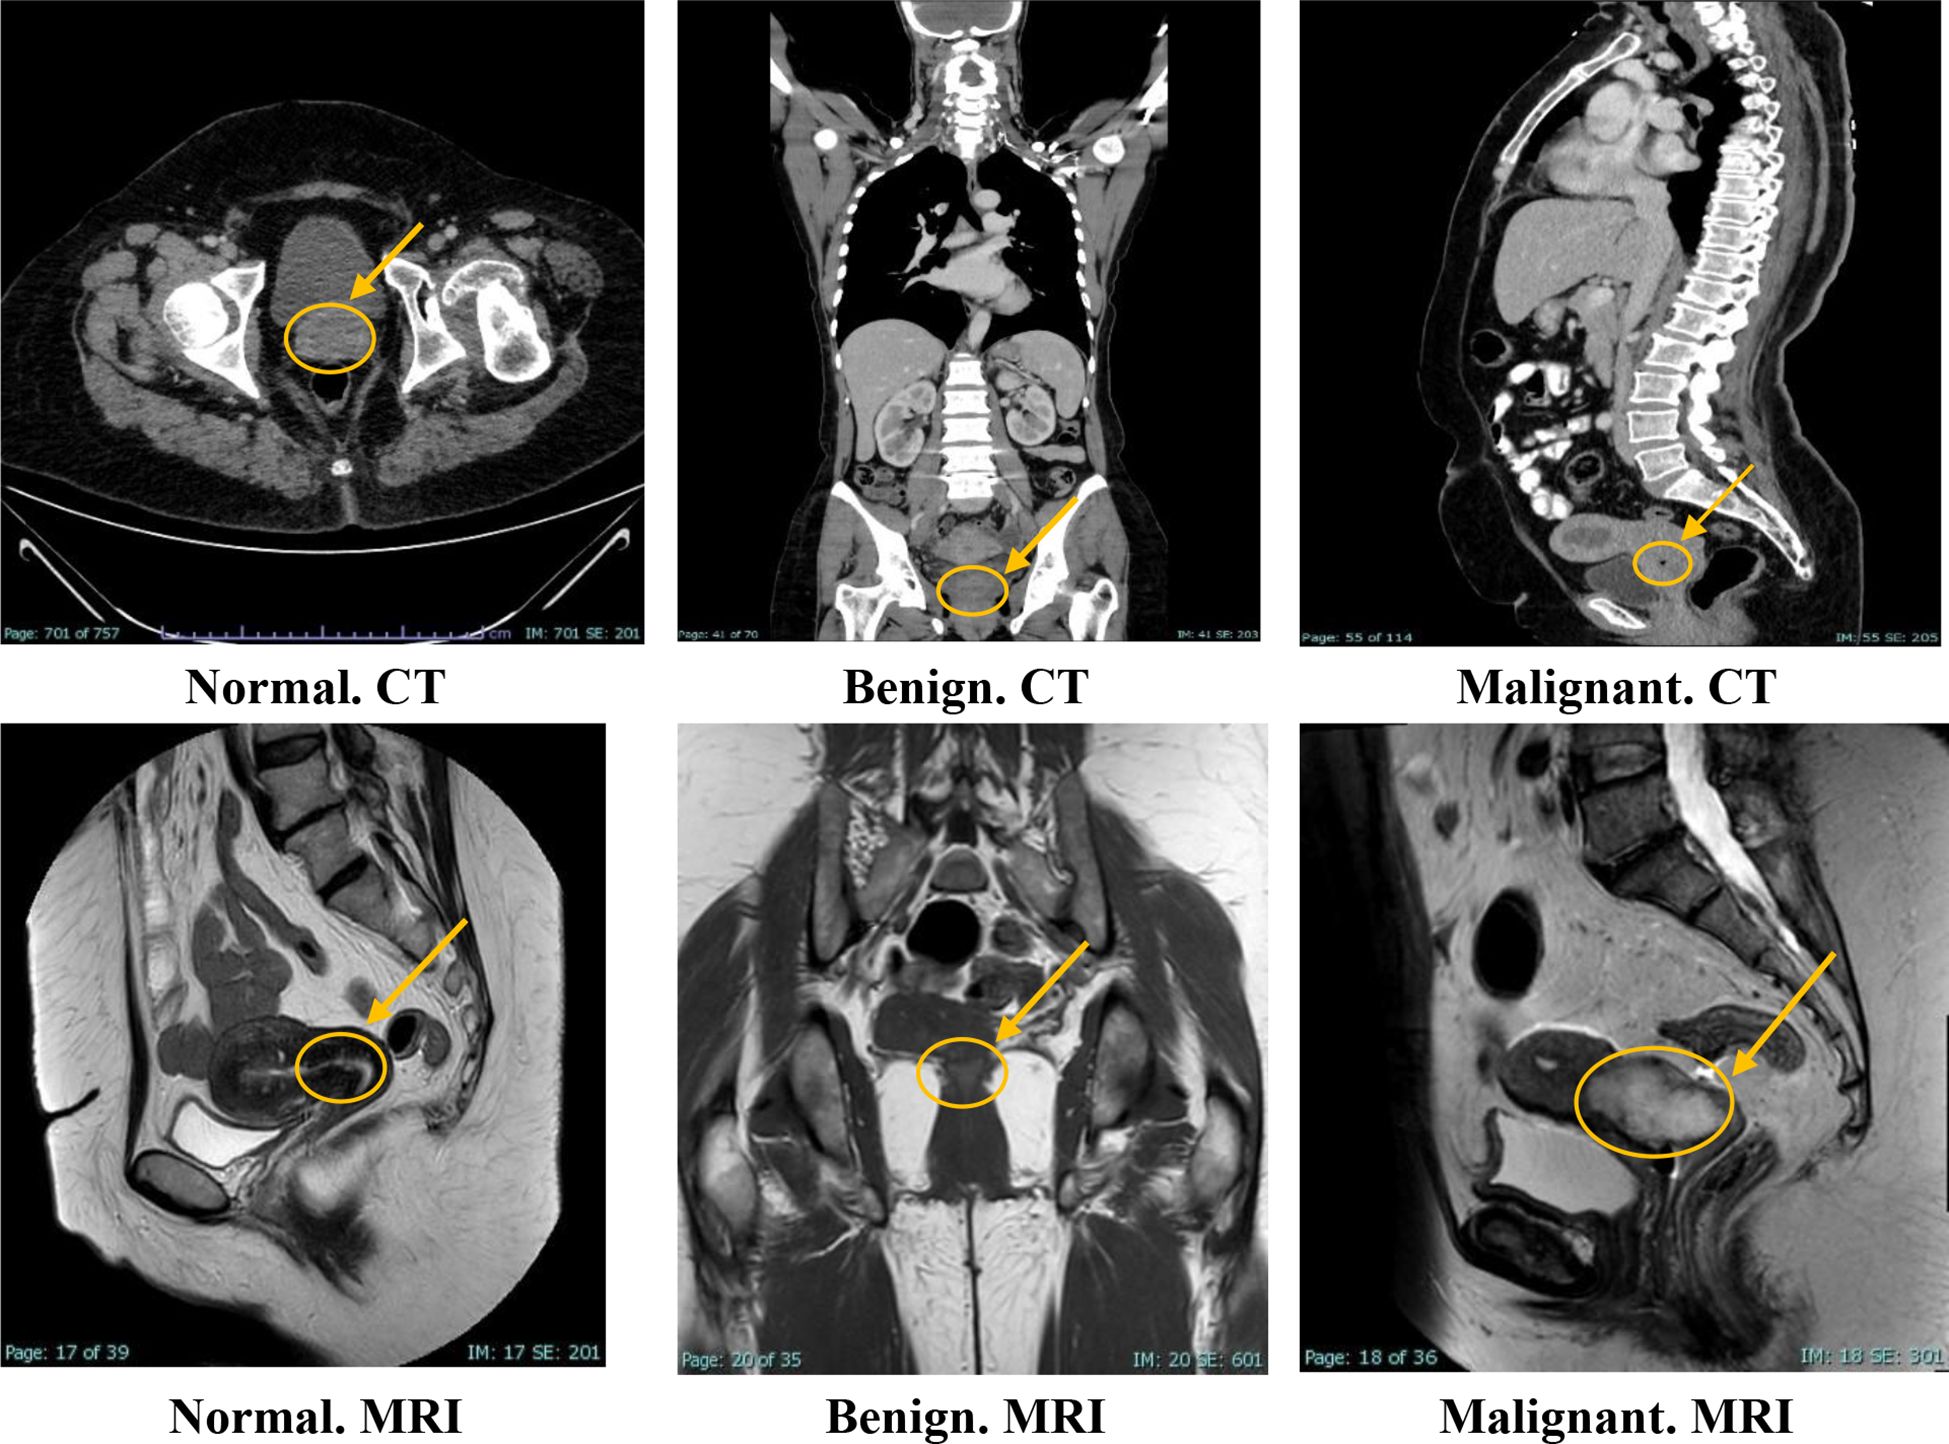

The KAUH-CCMD dataset includes MRI scans captured using an Ingenia Ambition 1.5T scanner. The KAUH-CCTD dataset includes CT scans stored on a Philips Brilliance 64-channel CT scanner. Both datasets contain 1,974 images each, classified into three groups: normal, benign, and malignant. Table 1 shows the distribution of the KAUH-CCTD and KAUH-CCMD datasets, while Figure 2 provides a sample from each dataset.

Figure 2

Sample from the KAUH-CCTD and KAUH-CCMD datasets.